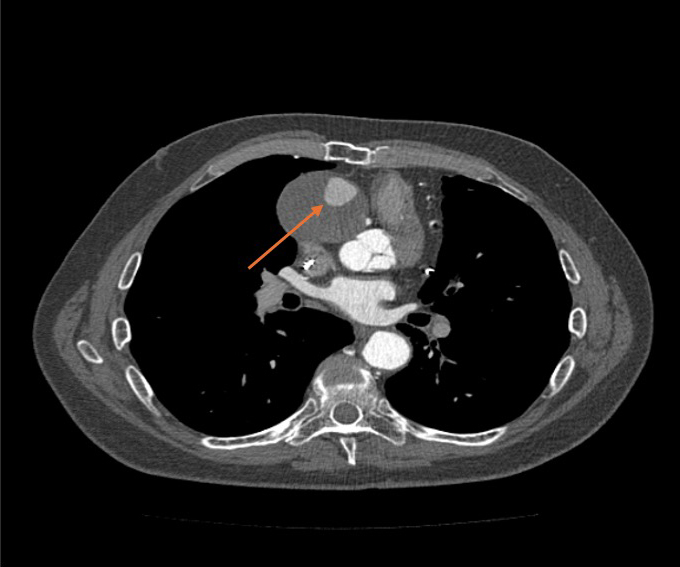

Figure 5

Figure 5. A thoracic computed tomography scan shows that blood flow is prevented by the uniform brightness throughout the aneurysm.